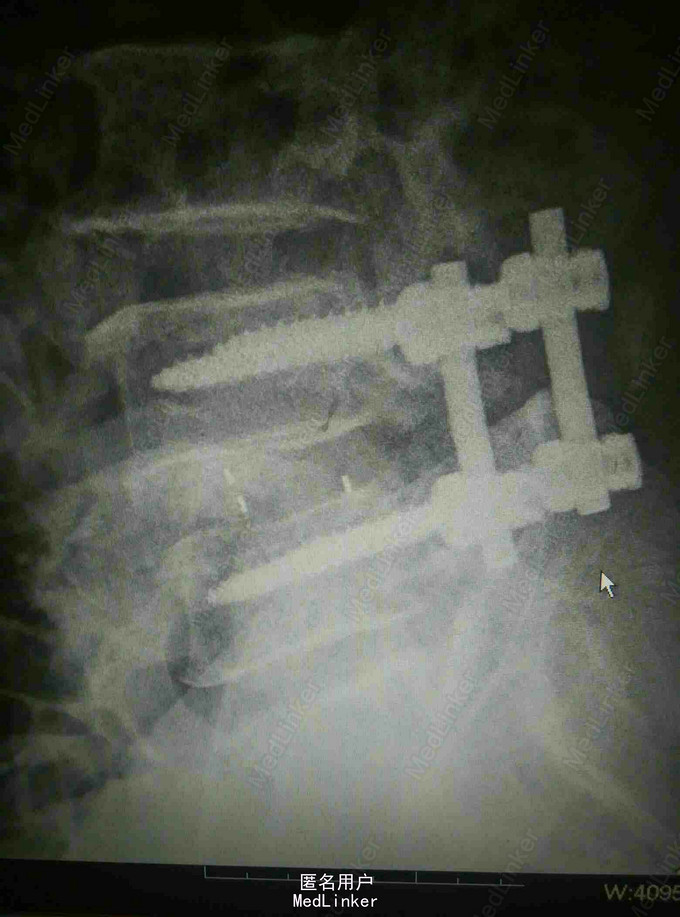

反复腰痛5年,加重伴跛行10余天 患者老年男性,5年前无明显诱因出现腰痛,休息后缓解,数年来反复发作,自行外用膏药对症治疗。近10余天来患者腰痛明显加重,伴跛行,右下肢疼痛,于当地医院就诊摄片提示腰椎退变,为进一步治疗入我院。

查体:腰4~5棘突及骶部压痛,无明显叩击痛,右大腿外侧疼痛,右足背外侧感觉减退,双下肢肌力正常,双侧直腿抬高实验阴性。 辅查:外院X线片提示腰椎退变 我院核磁提示腰4-5关节突增生内聚,椎间盘后突压迫硬膜囊及神经根

诊断:腰椎管狭窄 治疗:腰椎后路减压植骨内固定术